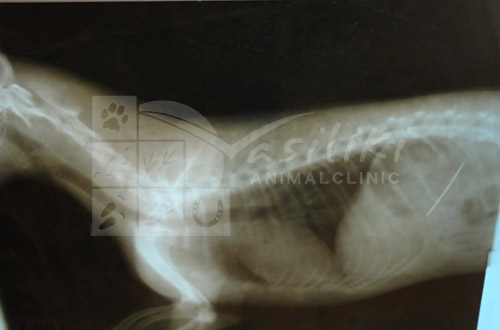

Τη συνέχεια είναι μάλλον εύκολο να την μαντέψετε. Ο μικρός Μπόνζο ήρθε στο ιατρείο όπου η πρώτη κιόλας ακτινογραφία έδειξε τη βελόνα να 'κάθεται' μέσα στο στομαχάκι του!

Ο Μπόνζο χειρουργήθηκε άμεσα αφού το μέγεθος της βελόνας ήταν τέτοιο που θα μπορούσε από στιγμή σε στιγμή να τρυπήσει τα εσωτερικά όργανα του ζώου . Η βελόνα βγήκε από το στομάχι του Μπόνζο 'άθικτη' μαζί με την κλωστή! Μάλλον δεν πρόλαβε να τελειώσει το 'ράψιμο' και τον πρόλαβε η βελόνα .............του χειρουργού!!!!!